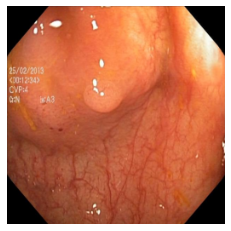

(a) Refer to caption Refer to caption Refer to caption Refer to caption Refer to caption Refer to caption

(b) Refer to caption Refer to caption Refer to caption Refer to caption Refer to caption Refer to caption

(c) Refer to caption Refer to caption Refer to caption Refer to caption Refer to caption Refer to caption

(d) Refer to caption Refer to caption Refer to caption Refer to caption Refer to caption Refer to caption

(e) Refer to caption Refer to caption Refer to caption Refer to caption Refer to caption Refer to caption

(f) Refer to caption Refer to caption Refer to caption Refer to caption Refer to caption Refer to caption

(g) Refer to caption Refer to caption Refer to caption Refer to caption Refer to caption Refer to caption

(h) Refer to caption Refer to caption Refer to caption Refer to caption Refer to caption Refer to caption

Figure 3: Sample data used and generated in the different steps of PolypConnect pipeline. (a) - real polyp images, (b) - manually annotated polyp masks, (c) - randomly selected colon images used as input to the final step of PolypConnect, (d) - extracted edge images of row c. (e) - extracted edge images of polyp regions of row a using the masks of row b. (f) - combined edge images of row d and f. (g) - generated polyp on the images of row c using EdgeConnect. (h) - generated samples from AOTGAN.